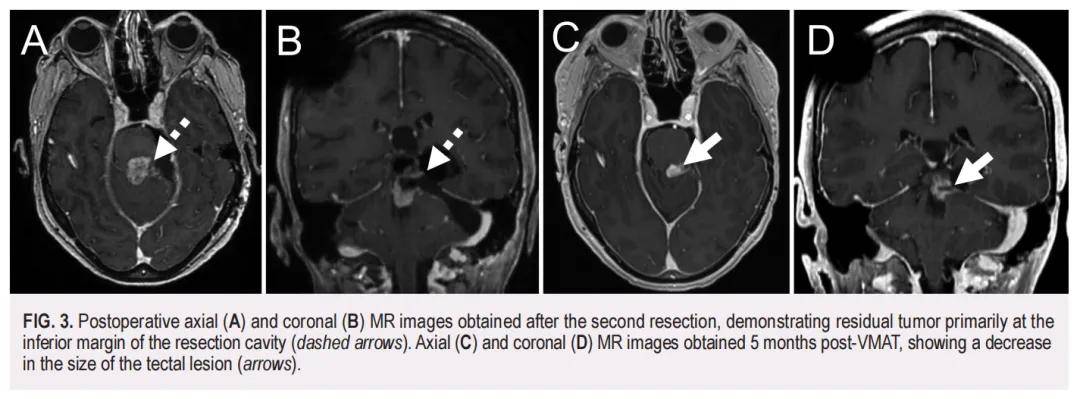

术后病理学检查证实为中分化鳞状细胞癌(SCC),其PD-L1综合阳性评分(CPS)<1%。此外,对切除的顶盖病变进行的NGS panel检测显示,SCC与原始表皮样囊肿(EC)存在相同变异,包括TP53(F113V,可能致病性)、CASP8[I315V,意义未明变异(VUS)]和MCL1(T38S,VUS)。进一步分析显示,该SCC的肿瘤突变负荷(TMB)为 14.9 muts/Mb。两个样本间的相同变异强烈提示两者存在共享的突变特征,并支持EC作为前体病变,其中致病性TP53突变促进了肿瘤发生。值得注意的是,SCC中还存在一个额外的PTEN变异(D92H,可能致病性),提示这是一个促成疾病进展的第二个驱动突变。在SCC样本中,TP53和PTEN突变的变异丰度(VAFs)分别高达 81% 和 79%。整体而言,这有力支持了初始EC的恶性转化。术后 2 个月的MRI显示,残留肿瘤主要位于切除腔下缘(图3A和B)。患者随后接受了容积调强弧形治疗(VMAT),针对原始EC、切除腔边缘及顶盖次全切除的强化区域,处方剂量为 54 Gy(分 30 次照射)。VMAT治疗后 5 个月的随访MRI显示治疗反应良好,顶盖病变体积缩小(图3C和D)。然而,VMAT治疗 1 年后,患者出现复视加重,并伴有右手和右脚麻木。此时MRI显示左侧顶盖不均质强化肿块出现间隔期增大(大小为 2.6×1.9×2.6 cm),并观察到中心扩散受限及动脉自旋标记(ASL)信号增强,提示肿瘤复发(图4)。后续PET/MRI显示该病灶有显著氟代脱氧葡萄糖摄取。

▲图3 第二次切除后获得的术后轴向(A)和冠状(B)MRI图像,显示残留肿瘤主要位于切除腔的下缘(虚线箭头)。VMAT 术后 5 个月获得的轴向(C)和冠状(D)MRI图像显示顶盖病变尺寸减小(箭头)